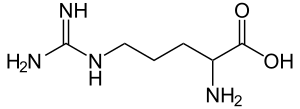

| Other names: Arginase deficiency[1] | |

| |

| Arginine | |

Argininemia is an autosomal recessive urea cycle disorder where a deficiency of the enzyme arginase causes a buildup of arginine and ammonia in the blood. Ammonia, which is formed when proteins are broken down in the body, is toxic if levels become too high; the nervous system is especially sensitive to the effects of excess ammonia.[2][6]

Mutations in the ARG1 gene cause argininemia, which belongs to a class of genetic diseases called urea cycle disorders.[4][5] The urea cycle is a sequence of reactions that occurs in liver cells (hepatocytes). This cycle processes excess nitrogen, generated when protein is used by the body, making urea that is excreted via the kidneys.[7]

The ARG1 gene provides instructions for making an enzyme called arginase, this enzyme controls the last steps of the urea cycle, which produces urea by extracting nitrogen from arginine.[4] In people with arginase deficiency, arginase is missing, and arginine is not broken down properly. consequently, urea cannot be produced and excess nitrogen accumulates in the blood in the form of ammonia. Ammonia and arginine are thought to cause neurological problems and other symptoms of arginase deficiency.[2]